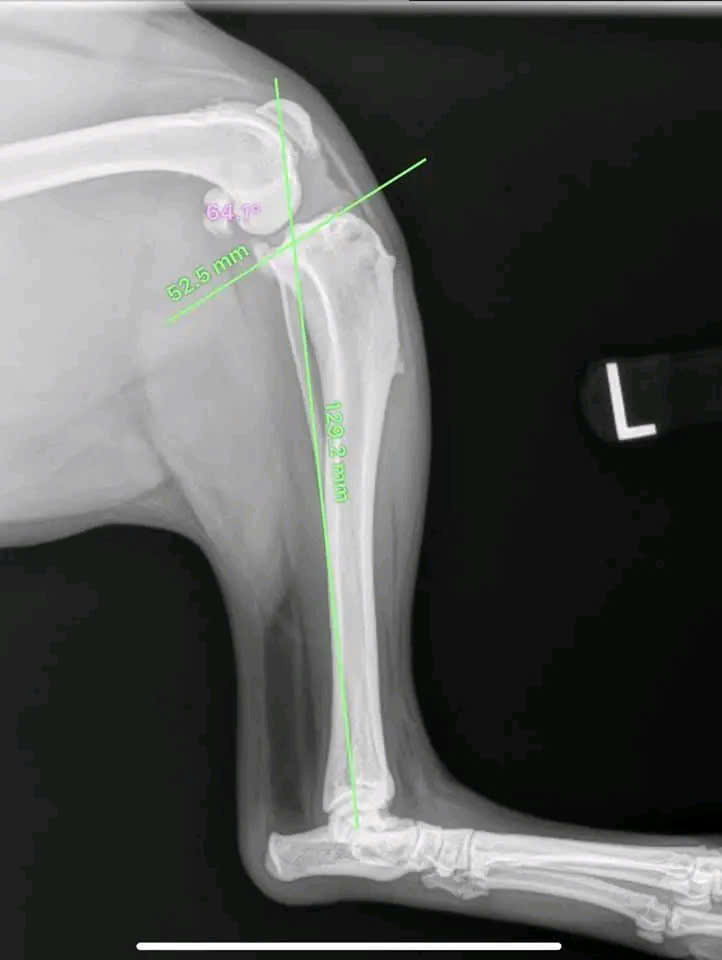

Hình ảnh thực tế

Khám phá không gian chăm sóc thú cưng chuyên nghiệp tại Bệnh viện Thú Y Gia Kiệm